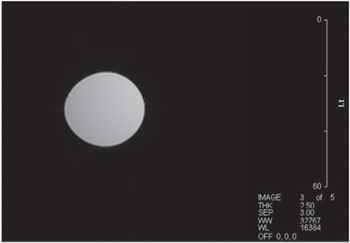

With the magnet operating stably, and with a good level of shim achieved, we performed some MRI images on fruit. We were able to achieve both spin-echo [19] as can be seen in figures 22 and 23 and gradient-echo [19] images as can be seen in figures 24 and 25.

Figure 22. Spin-echo image of 30 mm diameter spherical water sample. Axial image, 100 × 100 mm field of view (FOV). TR = 1500 ms, TE = 300 ms. 2.5 mm slice.

Download figure: